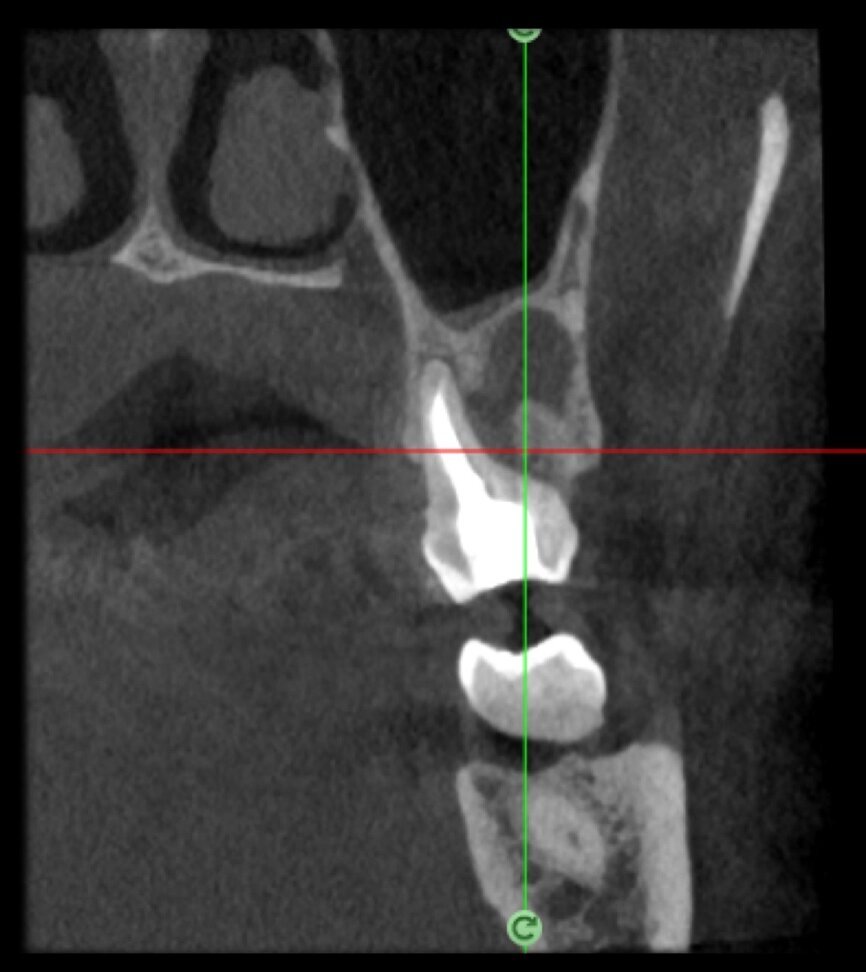

The case with which I would like to start my clinical review is a perfect example of how difficult it is to establish the origin of the patient’s symptoms on the basis of an intraoral radiograph alone. Not only does the 2D study fail to establish with certainty the presence of a lesion, but more importantly, it is impossible to establish the size, morphology and type of the lesion. An analysis of the 3D imaging, however, provides a clear picture of the clinical situation: the coronal and sagittal slices revealed the presence of a large lesion extending from the apex of the mesial root of this molar to the furcation, while the axial slices allow us to conduct a precise analysis of the endodontic anatomy and, in particular, the shape of the mesial root, which in this case was fused with the palatine root. A full overview of the case can, therefore, guide the decision-making process and direct the treatment plan towards a specific type of treatment (Figs. 1–4).